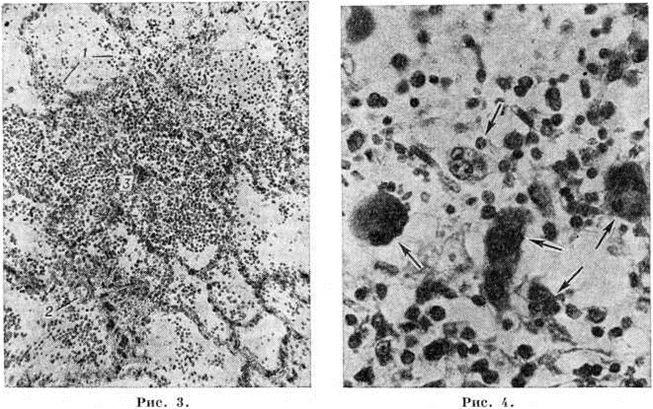

Могут встречаться мелкоочаговые, сливные бронхопневмонии и инфарктообразные пневмонии, а также некрозы ткани лёгкого. При пневмонии образуется фиброзно-геморрагический экссудат, который иногда содержит большое количество бластных клеток. В оболочках и веществе головного мозга при микроскопии выявляются лейкостазы, инфильтрация лейкозными клетками стенок сосудов с выходом их в периваскулярные пространства и формированием в ткани скоплений, часто с наличием эритроцитов. Иногда встречаются кровоизлияния без примеси бластов. Характерны тяжёлые дистрофические изменения ганглиозных клеток, в ряде случаев фокусы пролиферации глии. Может иметь место лейкозная инфильтрация по ходу черепных и спинальных нервов, в симпатических ганглиях. Больные острыми Лейкозы нелеченые или резистентные к терапии, часто умирают от малокровия и тяжёлой интоксикации, обусловленных прогрессированием заболевания. Высокий удельный вес среди причин смерти составляют поражение головного мозга, пневмонии и сепсис. В некоторых случаях смерть наступает вследствие глубоких нарушений функции различных органов (сердца, печени, почек, надпочечников), обусловленных массивным лейкозным поражением, обширными кровоизлияниями. Иногда больные погибают от массивных профузных кровотечений (носовые, кишечные, маточные), перфорации кишечника, разрыва селезёнки, обострения туберкулёза на фоне лейкозного процесса.

Острый миелобластный лейкоз в развёрнутой стадии болезни характеризуется выраженной лейкозной инфильтрацией костного мозга и других органов. В печени лейкозные разрастания локализуются в синусоидных капиллярах и в области портальных трактов. Аналогичное расположение инфильтратов имеется и при других более редких формах острого Лейкозы (монобластном, миеломонобластном, недифференцируемом, промиелоцитарном и другие), поэтому данный признак не может служить основанием для разграничения форм острого Лейкозы В лёгких лейкозная инфильтрация обычно выявляется по ходу межальвеолярных перегородок с выходом бластных клеток в просветы альвеол (рисунок 3), возможна локализация и в окружности бронхов, сосудов, междольковых перегородках. У детей при этой форме Лейкозы лейкозные разрастания в вилочковой железе располагаются в соединительнотканных прослойках, сдавливают дольки, что сопровождается увеличением количества аргирофильных волокон. У взрослых типично развитие множественных узлов в надкостнице плоских и трубчатых костей, почках, печени, половых железах, жировой клетчатке (подкожной, ретробульбарной, клетчатке большого сальника и малого таза), иногда в коже, конъюнктиве, твёрдой мозговой оболочке и костном мозге. В ряде случаев в области опухолевых узлов и системных поражений имеется зелёное окрашивание ткани (хлоролейкоз). Аналогичные изменения могут выявляться и при Лейкозы у детей.

При остром промиелоцитарном лейкозе резко выражен геморрагический синдром, и кровоизлияния в жизненно важные органы являются основной причиной смерти. Макроскопические признаки лейкозного поражения часто отсутствуют. При микроскопическом исследовании лейкозная инфильтрация в большинстве случаев не выходит за пределы кроветворных органов. Этой форме не свойственно развитие узловатых разрастаний. Инфильтраты состоят из бластных клеток, содержащих в цитоплазме грубую фиолетово-бурую зернистость.

При остром мегакариобластном лейкозе в костном мозге выявляется большое количество атипичных мегакариоцитов и мегакариобластов, которые диффузно рассеяны в ткани, а местами образуют скопления (рисунок 4). Такие же клетки в значительном количестве содержатся в ткани и синусах селезёнки, лимфатических, узлов, просветах мелких сосудов печени, лёгких и других органов.

Острый эритромиелоз характеризуется системной пролиферацией ядерных клеток красного ряда костного мозга, часто с преобладанием среди них эритрокариоцитов. Одновременно отмечается увеличение количества незрелых клеток миелоидного ряда, преимущественно миелобластов.

При всех формах Лейкозы наиболее интенсивное подавление лейкозной инфильтрации наблюдается в костном мозге. При вскрытии костный мозг плоских костей очагово или на всем протяжении суховатый, серого или серо-жёлтого цвета, в нем имеются участки жировой ткани и тёмно-красные поля кровоизлияний. При микроскопическом исследовании количество клеток в костном мозге снижено, видны поля опустошения различной величины, состоящие из отёчной стромы с наличием макрофагов и единичных бластных клеток (рисунок 8), зоны геморрагического пропитывания. Лейкозные инфильтраты располагаются очагово, содержат много клеток в состоянии лизиса, пикноза, распада (рисунок 9). Могут встречаться очаги некроза, представленные распадающимися лейкозными клетками, а также участки тотального коагуляционного некроза ткани с одновременной гибелью стромы. Иногда видны гигантские клетки с уродливыми гиперхромными ядрами, появление которых связывают с дистрофическими изменениями бластных элементов. Такие же клетки иногда выявляются в других органах.